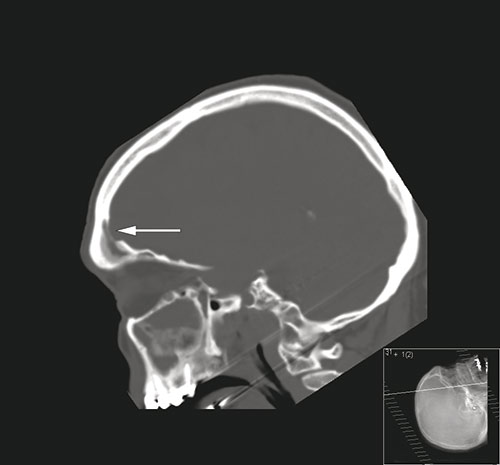

En mann i 60-årsalderen ble innlagt på lokalsykehus etter at han ble funnet konfus og med redusert bevissthet. Han hadde da ifølge komparentopplysninger hatt hodepine i to dager. Ved undersøkelse var han høyfebril (40,5 °C) og nakkestiv. Glasgow Coma Scale ble vurdert til 12. Den nevrologiske undersøkelsen var ellers upåfallende. Cerebral CT tatt med beinvindu i sagittalplan (bilde til venstre) viste fortetning i sinus frontalis og beindefekt (pil) inn mot epiduralrommet. Cerebral MR tatt med T1-vekting etter intravenøs kontrast (bilde til høyre) viste venstresidig subdural væskeeffusjon (hvit pil), kontrastladning i dura (rød pil) og signalforandringer (stjerne) i venstre frontallapp. Spinalvæsken var blakket med hvite blodceller på 2187 · 10⁶/l (normalt 0 – 5) og totalprotein på 1,55 g/l (normalt 0,15 – 0,50). På mistanke om subduralt empyem og cerebritt ble pasienten satt på antibiotika og overflyttet til universitetssykehus. Der ble han operert med kraniotomi og drenasje av empyem samt tetting av beindefekt i os frontale. Dyrkning av puss viste Streptococcus intermedius (Milleri).

Subduralt empyem gir ofte høy feber, hodepine, redusert bevissthet og kan gi fokalnevrologiske utfall og kramper. Det kan forårsakes av spredning av bakteriell sinusitt gjennom erosjon av beinbarrierer til epiduralrommet (1). Cerebral MR er den mest sensitive metoden for påvisning av cerebrale infeksjonssykdommer (2) og det er avgjørende at pasienter med påvist empyem eller abscess henvises raskt til kirurgisk drenasje (1).